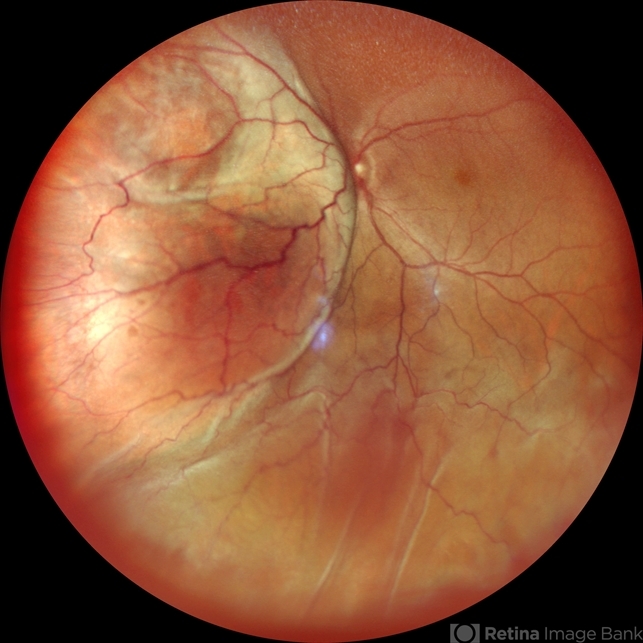

Co-author(s): Dr. Manish Nagpal, Dr. Navneet Mehrotra - Retina Foundation, Ahmedabad - Uploaded on Sep 8, 2021.

- Choroidal Melanoma

Scanning laser ophthalmoscope

Nidek Mirante - Description

- Wide field photograph of a 45 year-old female presented with diminution of vision in left eye for 1 month and on examination she had intraocular melanotic mass with exudative retinal detachment.